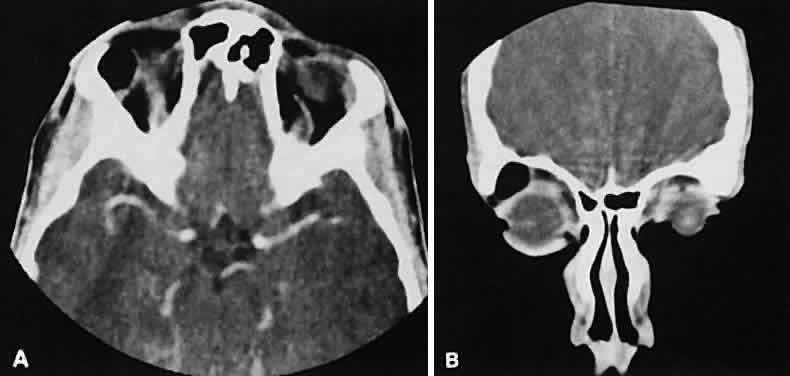

Radiographic evaluation can show either infiltrative or circumscribed masses. Some tumors display a predilection for metastasizing to certain structures, such as prostate carcinoma to bone and cutaneous melanoma to EOMs (Fig. 21). Evidence of bilateral disease at presentation ranges from 7% to 9%, with the prime example being neuroblastoma.71

Fig. 21. A. Axial view shows bilateral involvement from metastatic breast carcinoma. An amorphous infiltrative soft-tissue mass is more apparent in the right orbit, which encases the globe, producing clinical and radiographic enophthalmos. Cutaneous melanoma metastatic to the superior rectus muscle is depicted on axial (B) and coronal (C) views. A locally enhancing and asymmetric enlargement is restricted to the right superior rectus muscle. These features distinguish this lesion from Graves' orbitopathy.